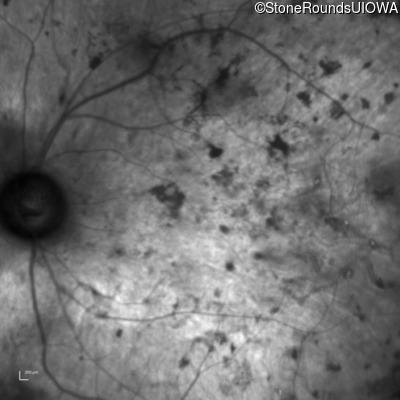

Age at visit: 28 years